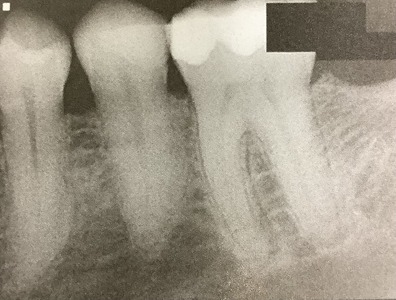

最近に根管治療をした6番も、押しても何ともありません。